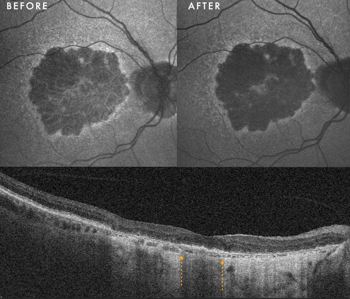

Clinical presentation: A 60-year-old woman presented with large, central drusenoid PEDs in both eyes. Natural history data indicate that the resolution of such lesions is almost invariably accompanied by atrophy of the underlying RPE and overlying photoreceptors.

Response to therapy: Following PBM, one eye exhibited a remarkable anatomical response: the PED resolved and flattened, accompanied by a significant restoration of the ellipsoid zone on OCT. Crucially, this occurred without the expected RPE atrophy (See Fig 1 at the top of this article).

This structural success was matched functionally, with BCVA improving from 6/9 to 6/6. In the fellow eye, the PED remained structurally stable, yet she still achieved functional gain, improving from 6/30 to 6/24.